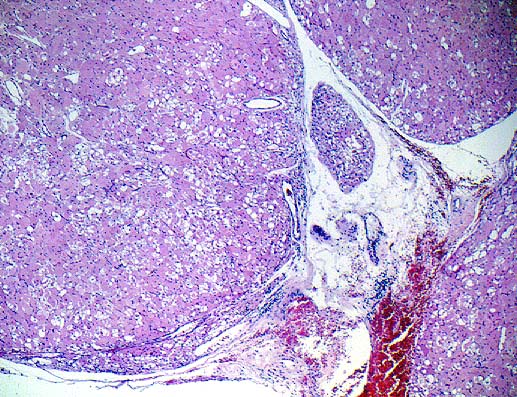

The patient is a 64-year old male who presented with a five-month history of dysphagia of solids greater than liquids. He denied pain, recent and remote trauma. An endoscopy revealed a prominent mucosa-covered lesion near the vocal cords. A CT scan revealed a large, bulky, well-circumscribed tumor involving the right pyriform sinus, postcricoid hypopharynx and right preepiglottic space. He had no cervical lymphadenopathy.